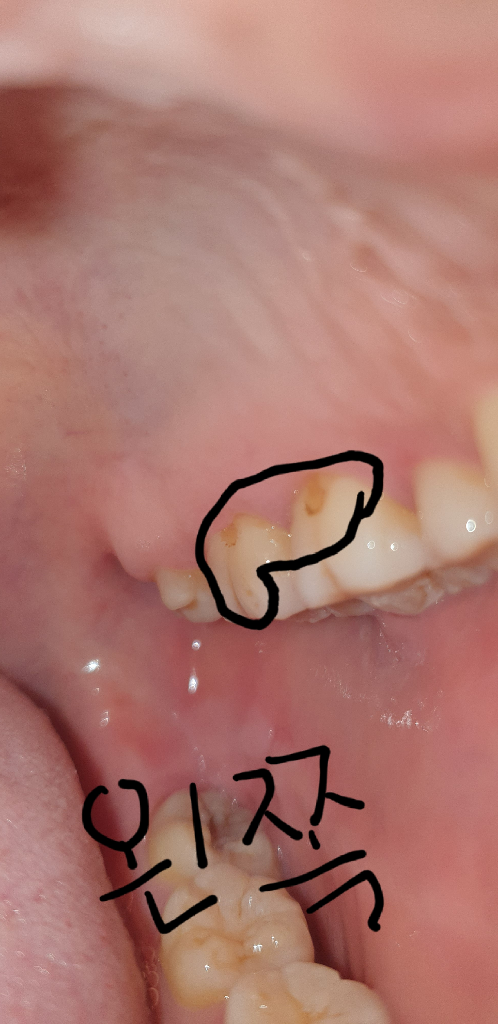

치경부 마모증으로 인해서 그부위에 착색이 된거 같습니다. 저럴경우에는 스켈링으로 제거하거나 마취후에 제거후에 레진으로 치료를 하시는게 좋습니다.

사진상으로는 정확히 보이지 않지만 치아 마모에 의해서 나타날 수도 있을 것으로 보이며 특정한 물질에 노출되어서도 나타날 수 있어 보입니다. 따라서 해당 부분에 대해서는 치과 방문 후 상담을 받아보는 것이 필요합니다. 단순히 갈아 내서 될 문제인지 평가가 필요합니다.